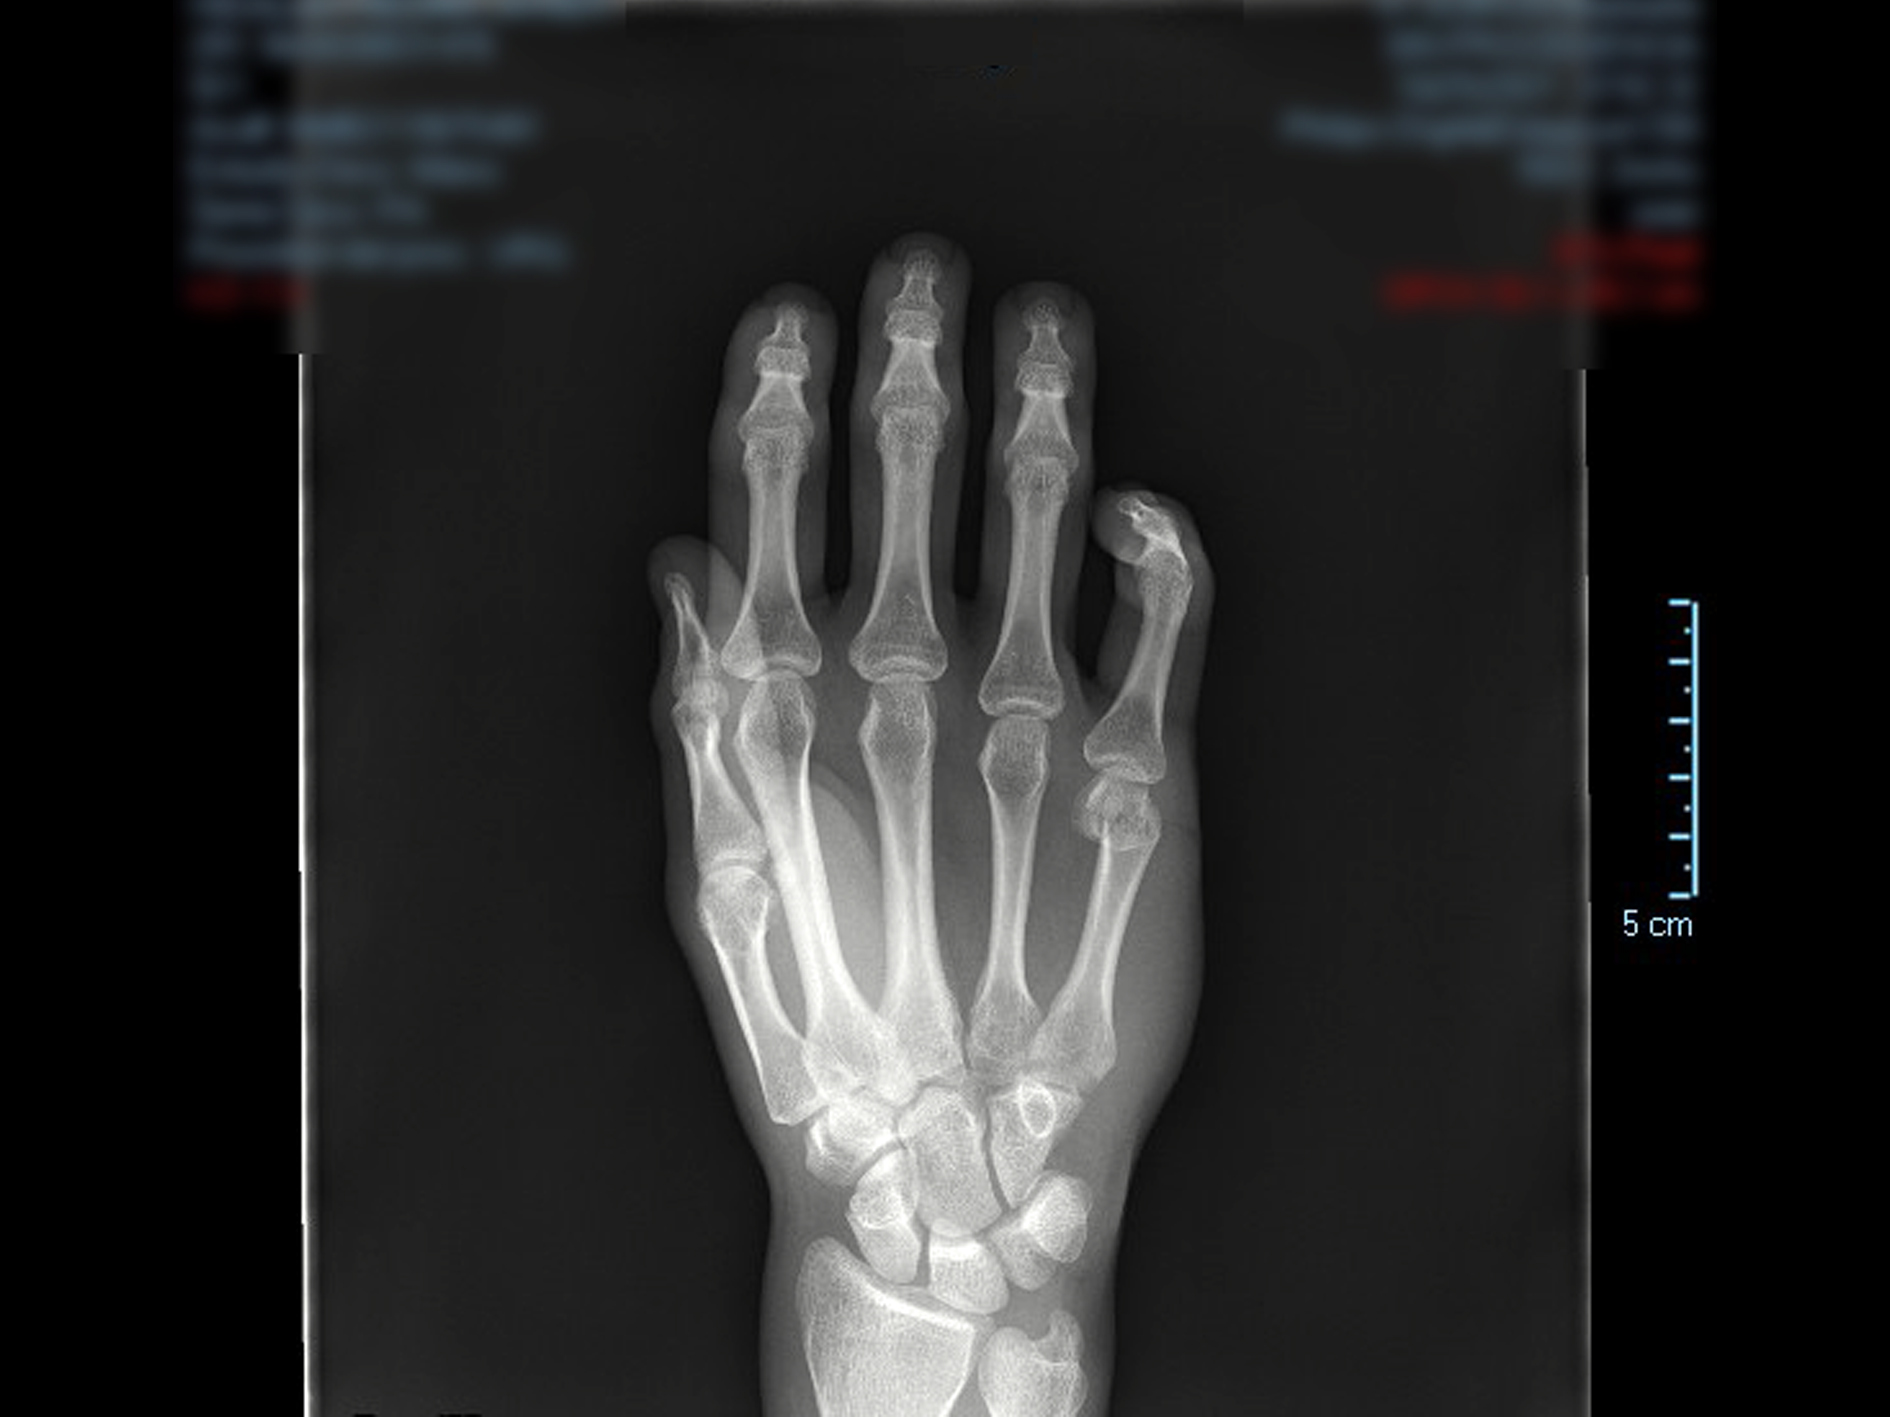

El Miembro Superior en ámbito médico abarca la extensión de los brazos y las subdivisiones que los componen: hombro, codo, muñeca y dedos. "La evolución del ser humano ha permitido la sofisticación de los movimientos del miembro superior permitiendo acciones exclusivas de nuestra especie. Su funcionalidad en nuestra actividad diaria es esencial, desde los gestos más simples a movimientos de máxima dificultad. Cuando aflora una lesión, la perdida de autonomía es inmediata e incluso puede ser incapacitante, de ahí que sea motivo frecuente de consulta", detalla el especialista.

Las patologías más habituales suelen ser fracturas, Luxaciones y subluxaciones, tendinopatías, bursitis, neuropatías... Todas ellas tienen respuesta en el nuevo modelo de atención al paciente especializado en las patologías del Miembro Superior. "Cuando acude por primera vez al médico se activa un modelo de diagnóstico y recuperación planificado personalmente para cada paciente en el que se implican distintos especialistas del centro sanitario (Traumatología, Medicina Física y Rehabilitación Reumatología, Nutrición, Rehabilitación y Fisioterapia)", explica la fisioterapeuta, Belén Aranda Jimenez. La especialista destaca la labor de coordinación y trabajo transversal de la Unidad del Miembro Superior; "trabajamos de forma coordinada para establecer el mejor abordaje posible y garantizar una recuperación optima".

- Cirugía reconstructiva de fracturas complejas del Miembro Superior